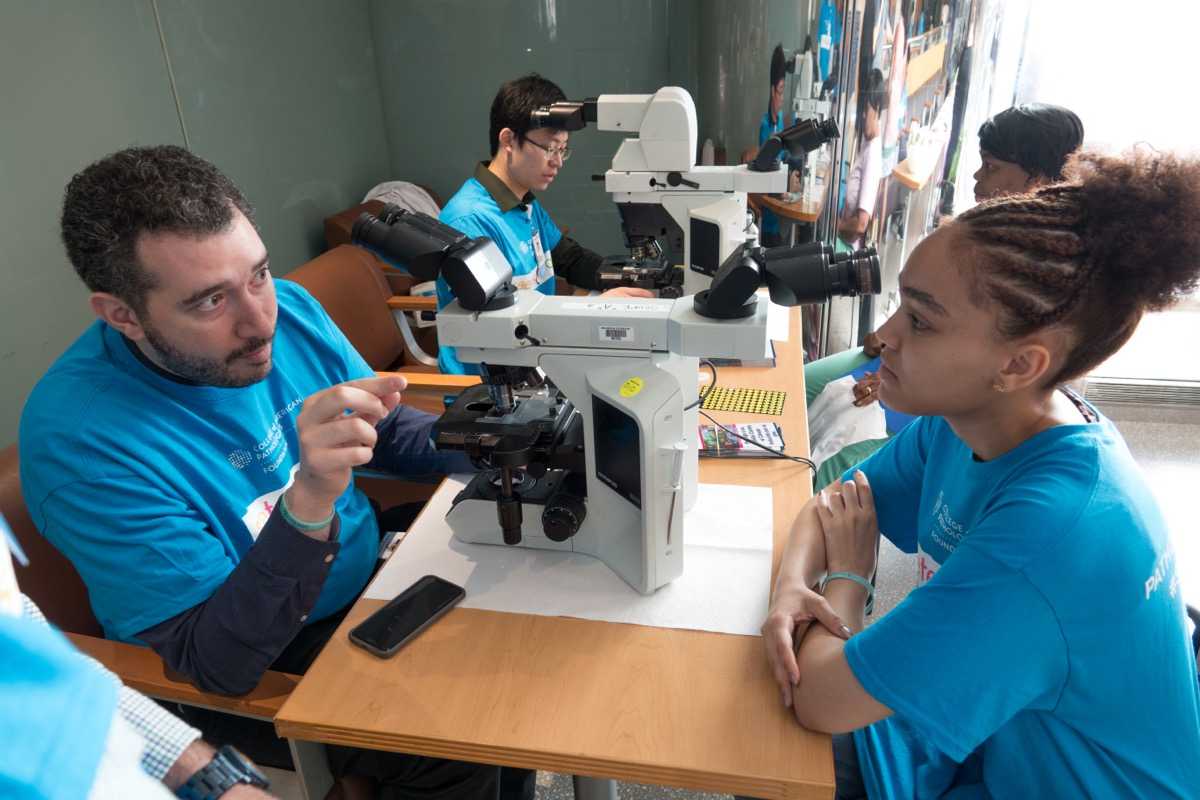

The Pathology Fellowship Programs at Montefiore Einstein offer trainees a collegial learning environment that fosters collaboration, mentorship, creativity and excellence in clinical, scientific and academic settings. Hailing from among the world’s most prestigious medical institutions, our faculty and fellows provide evidence-based, high-quality care to a diverse Bronx patient population. Graduates leave our program well prepared and confident in their ability to perform as highly skilled, compassionate diagnostic clinicians, physician-scientists and valued members of any healthcare team.

Dr. Antonio Cajigas, Cytopathology Fellowship Program Director

Our curriculum offers fellows groundbreaking, state-of-the-art laboratory techniques and cutting-edge approaches to diagnostic medicine, as well as frequent opportunities for independent research. Fellows are supported by faculty members committed to helping them bring their scientific vision to life. Novel research projects are featured in departmental works-in-progress sessions, presented at professional meetings, published in peer-reviewed journals and entered in award competitions.

As a premier academic medical center serving the Bronx, Westchester and the Hudson Valley, Montefiore Einstein offers its postgraduate trainees comprehensive exposure to a broad diversity of patients and pathologies. The diverse range of experience available prepares our postgraduate trainees for future careers in their chosen field, be it in the research or clinical and/or non-clinical setting.